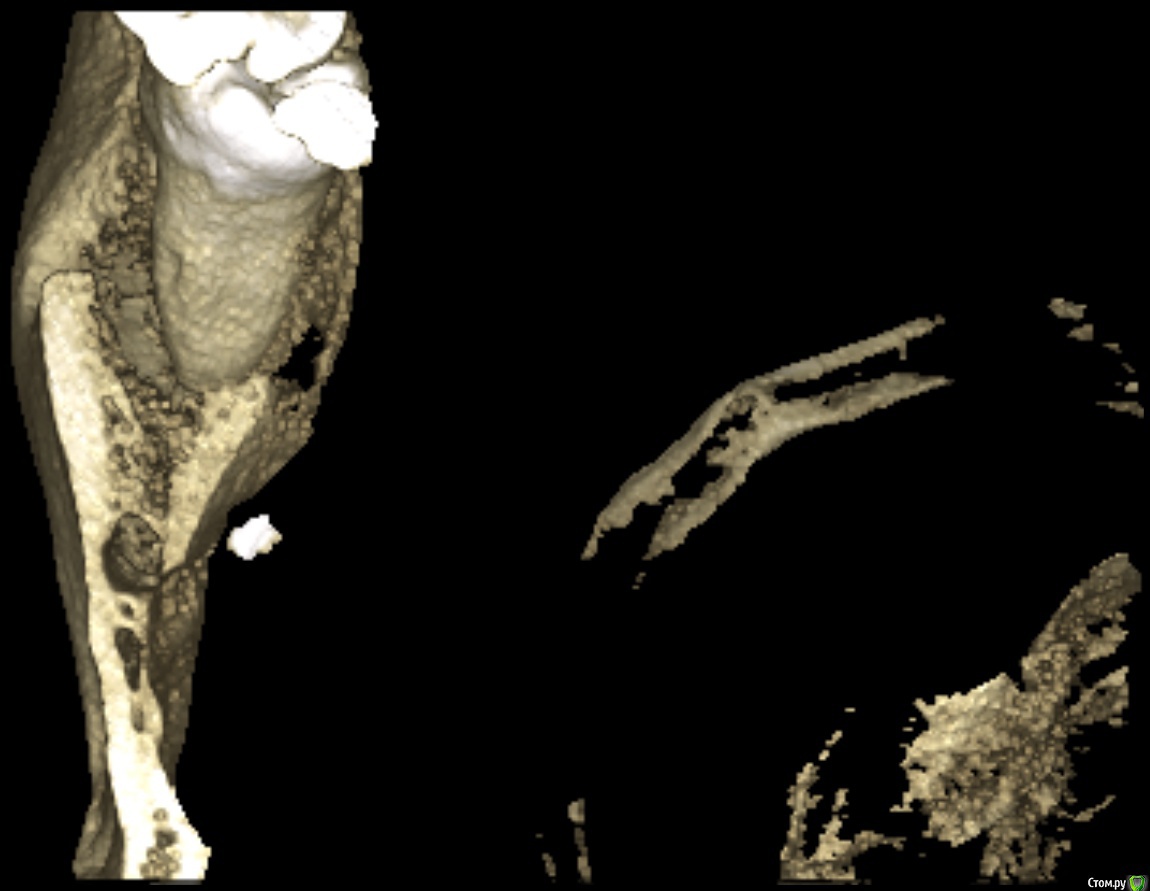

medbratec Опубликовано 9 октября, 2016 Поделиться Опубликовано 9 октября, 2016 (изменено) Предыстория:к 30 годам вылезла наконец часть 38-го. Пару лет с переменным успехом я боролся с воспалением капюшона (перикоронит как я понял называется) без помощи специалистов. Наконец решил избавиться от него радикально - удалением зуба.Зуб обломали, после пытались остатки вытащить в течении 3 часов, шатали/стучали и прочее, пока я сам не прервал экзекуцию. Затем направление в челюстно-лицевую, бормашина и т.д. И так, 20 июля проведена операция после неполного удаления 38 зуба. Через неделю был выписан. Еще через 2 недели обратился повторно с жалобами на не проходящую припухлость, сочение из лунки сукровицы и периодическую ноющую боль. Был проведен осмотр с применением инструментов и анестезии, достали осколок, сказали что воспаления надкостницы нет, назначили УВЧ. Провел физиопроцедуру в количестве 15шт. Стало лучше, даже начал жевать на обе стороны, чувство дискомфорта уменьшилось, реакция на горячее/холодное уменьшилась.В конце сентября загриповал и все симптомы обострились снова. На днях посетил специалиста, сделал снимок(прикреплен).Описание : На Р-грамме левой ветви нижней челюсти в косой проекции замыкательные пластины нижней челюсти не изменены. В толще тела определяется плотное инородное тело 0.3*0.1см.Специалист изучив снимок сказал, что по всей видимости в воспалительный процесс вовлечен соседний с удаленным зубом. Предлагает депульпировать 7-мерку, а затем провести операцию по костной пластике для заполнения полости от 8-ки, и добавив тем самым опору для 7-ки, попутно попытаться достать осколок косточки(инородное тело).В этот же день я был еще в одной клинике, где мне так же предложили 7-ку депульпировать для начала, а про инородное тело сказали, что это скорее всего обломан инструмент, предположительно зонд и стоит 10 раз подумать доставать ли его. Симптоматика на сегодняшний день:со стороны удаления воспалена миндалина, причем воспаление после выпиливания, а это уже более 2-ух месяцев, так полностью и не проходило. Увеличены лимфоузлы возле скулы и уха. Глотаю без болей.Болезненная реакция на горячее/холодное не только 7-ки, но и 3,4 зуба(сразу оговорюсь они раньше не реагировали да и внешне здоровы). При постукивании металлом 7-ка наиболее болезненна. Так же у 7-го боль при сильном нажиме, жевании сухарей например. Еще 7-ой стал заметно качаться. Чистка зубов неприятных ощущений не вызывает. На кислое, сладкое и прочие раздражители реакция слабая.Внешне в районе скулы есть еле заметная припухлость. При пальпации в месте удаления незначительные болевые ощущения.Испытываю скорее дискомфорт, чем боль при открытии рта и улыбке. Из лунки сочиться сукровица и видны кусочки тканей (возможно выгнивающей). На внешней стороне лунки наблюдается что-то похожее на флюс(надувется/здувается в течении дня, а также изменяет свой объем и плотность во время пальпации щеки снаружи).Головные боли, небольшая температура преимущественно в первой половине дня, нарушение сна, слабость. Я не медик, однако озвучу свои мысли по поводу лечения - вскрыть предполагаемый флюс, провести дезинфекцию, наложить швы, оставить дренаж на некоторое время. Параллельно антибиотикотерапия и электрофорез челюсти. Если все наладиться, то провести костную пластику с целью укрепления "посадочного места" 7-ки и скрытия его корней со стороны лунки. В данный момент я в растерянности. Хотел бы услышать мнение по поводу инородного тела - это осколок кости или обломок инструмента, что с этим делать, нужно ли его доставать, может ли он являться причиной воспаления, а не 7-мой зуб ?Очень не хочется напрасно омертвлять 7-ку. Какую стратегию лечения можете посоветовать ? п.с. постараюсь к вечеру сделать фото места удаления зуба. Изменено 9 октября, 2016 пользователем medbratec Ссылка на комментарий

Kazankov.Egor Опубликовано 9 октября, 2016 Поделиться Опубликовано 9 октября, 2016 Предыстория:к 30 годам вылезла наконец часть 38-го. Пару лет с переменным успехом я боролся с воспалением капюшона (перикоронит как я понял называется) без помощи специалистов. Наконец решил избавиться от него радикально - удалением зуба.Зуб обломали, после пытались остатки вытащить в течении 3 часов, шатали/стучали и прочее, пока я сам не прервал экзекуцию. Затем направление в челюстно-лицевую, бормашина и т.д. И так, 20 июля проведена операция после неполного удаления 38 зуба. Через неделю был выписан. Еще через 2 недели обратился повторно с жалобами на не проходящую припухлость, сочение из лунки сукровицы и периодическую ноющую боль. Был проведен осмотр с применением инструментов и анестезии, достали осколок, сказали что воспаления надкостницы нет, назначили УВЧ. Провел физиопроцедуру в количестве 15шт. Стало лучше, даже начал жевать на обе стороны, чувство дискомфорта уменьшилось, реакция на горячее/холодное уменьшилась.В конце сентября загриповал и все симптомы обострились снова. На днях посетил специалиста, сделал снимок(прикреплен).Описание : На Р-грамме левой ветви нижней челюсти в косой проекции замыкательные пластины нижней челюсти не изменены. В толще тела определяется плотное инородное тело 0.3*0.1см.Специалист изучив снимок сказал, что по всей видимости в воспалительный процесс вовлечен соседний с удаленным зубом. Предлагает депульпировать 7-мерку, а затем провести операцию по костной пластике для заполнения полости от 8-ки, и добавив тем самым опору для 7-ки, попутно попытаться достать осколок косточки(инородное тело).В этот же день я был еще в одной клинике, где мне так же предложили 7-ку депульпировать для начала, а про инородное тело сказали, что это скорее всего обломан инструмент, предположительно зонд и стоит 10 раз подумать доставать ли его. Симптоматика на сегодняшний день:со стороны удаления воспалена миндалина, причем воспаление после выпиливания, а это уже более 2-ух месяцев, так полностью и не проходило. Увеличены лимфоузлы возле скулы и уха. Глотаю без болей.Болезненная реакция на горячее/холодное не только 7-ки, но и 3,4 зуба(сразу оговорюсь они раньше не реагировали да и внешне здоровы). При постукивании металлом 7-ка наиболее болезненна. Так же у 7-го боль при сильном нажиме, жевании сухарей например. Еще 7-ой стал заметно качаться. Чистка зубов неприятных ощущений не вызывает. На кислое, сладкое и прочие раздражители реакция слабая.Внешне в районе скулы есть еле заметная припухлость. При пальпации в месте удаления незначительные болевые ощущения.Испытываю скорее дискомфорт, чем боль при открытии рта и улыбке. Из лунки сочиться сукровица и видны кусочки тканей (возможно выгнивающей). На внешней стороне лунки наблюдается что-то похожее на флюс(надувется/здувается в течении дня, а также изменяет свой объем и плотность во время пальпации щеки снаружи).Головные боли, небольшая температура преимущественно в первой половине дня, нарушение сна, слабость. Я не медик, однако озвучу свои мысли по поводу лечения - вскрыть предполагаемый флюс, провести дезинфекцию, наложить швы, оставить дренаж на некоторое время. Параллельно антибиотикотерапия и электрофорез челюсти. Если все наладиться, то провести костную пластику с целью укрепления "посадочного места" 7-ки и скрытия его корней со стороны лунки. В данный момент я в растерянности. Хотел бы услышать мнение по поводу инородного тела - это осколок кости или обломок инструмента, что с этим делать, нужно ли его доставать, может ли он являться причиной воспаления, а не 7-мой зуб ?Очень не хочется напрасно омертвлять 7-ку. Какую стратегию лечения можете посоветовать ? п.с. постараюсь к вечеру сделать фото места удаления зуба.Инородное тело металлической плотности, скорее всего инструмент, удаление его является приоритетом при наличии жалоб, а таковые имеют место быть. Ссылка на комментарий

medbratec Опубликовано 12 октября, 2016 Автор Поделиться Опубликовано 12 октября, 2016 Был на консультации в частной клинике.Вердикт - семерку лучше пока не трогать, ее чувствительность обусловлена оголенными корнями. Проводить ревизию лунки, доставать осколок вежливо отказались, и отправляют с этим в челюстно-лицевую.Посоветовали сделать клкт для прояснения картины. Я сделал, однако повторную консультацию пришлось отложить. Не знаю как оттуда вытащить картинки. Если кому будет не лень, то оставлю ссылку на скачивание образа диска. (600мб)Рентгенолог сказал, что осколок в мягких тканях, причем с внутренней стороны, также обнаружилась кариозная полость в месте соприкосновения 7-го и 6-го зуба. Ссылка на комментарий

medbratec Опубликовано 13 октября, 2016 Автор Поделиться Опубликовано 13 октября, 2016 Я вас прекрасно понимаю. Был бы специалистом, то так сразу и сделал. Просто не знаю, что конкретно и под каким углом показывать. Сделал несколько скриншотов. Напишите, если они окажутся не слишком информативны. Ссылка на комментарий

medbratec Опубликовано 13 октября, 2016 Автор Поделиться Опубликовано 13 октября, 2016 Ссылка на комментарий

IvanK Опубликовано 14 октября, 2016 Поделиться Опубликовано 14 октября, 2016 скорее всего , это пломбировочный материал, лежит он не в костной ткани, а в мягких тканях, если не беспокоит, то можно не трогать 1 Ссылка на комментарий

red_butler Опубликовано 17 октября, 2016 Поделиться Опубликовано 17 октября, 2016 если это пломбировочный материал то на снимках "до" он должен быть, но я вижу там что то металлическое 2 Ссылка на комментарий

kramer Опубликовано 22 октября, 2016 Поделиться Опубликовано 22 октября, 2016 если это пломбировочный материал то на снимках "до" он должен быть, но я вижу там что то металлическоеЧисто по снимку похоже на кончик твердосплавного бора. ИМХО. Ссылка на комментарий